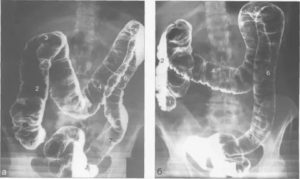

- рентген (помогает исключить непроходимость, а также определить наличие и размер каловых камней).

- рентгенографию;

- ирригоскопию;

Для оценкидвигательной функции кишечниканазначают рентгенографию с применением контрастного вещества (например,сульфата бария). Чтобы исключить органическую причину развития атонии,прибегают к:

- ирригоскопии;